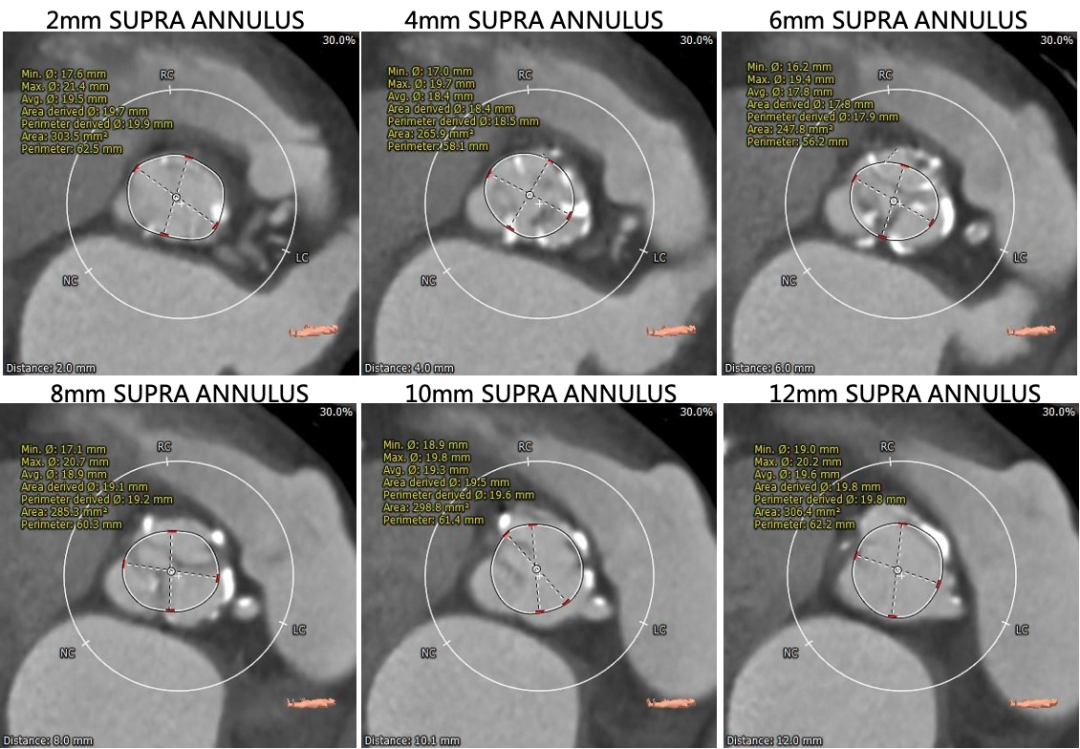

瓣环上多平面测量

术前CT显示为三叶式主动脉瓣,瓣膜钙化、瓣叶增厚,伴左-右及左-无瓣叶融合,左右冠脉开口较低,瓣叶冗长,冠脉闭塞风险高,同时合并冠状动脉及主动脉的严重钙化。

瓣环水平夹角为52°,降主动脉全程满布钙化斑块,双侧股动脉散在钙化斑块,血管入路直径偏小,最细处仅为5.5mm。

主动脉根部测量

冠脉高度、瓣叶长度及钙化测量

外周血管及主动脉弓解剖